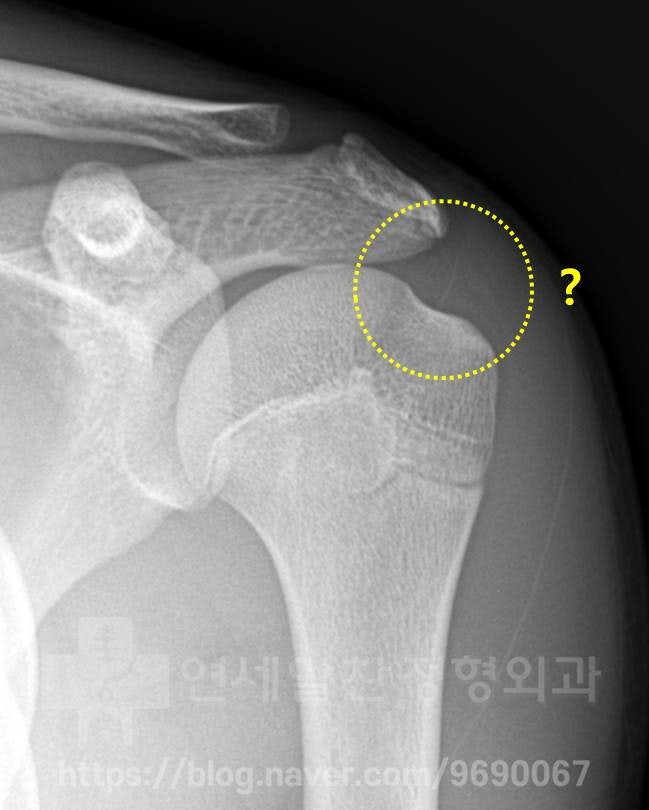

X-ray 사진에서 보았을때 전혀 문제 없는 정상적인 소견이 관찰되었습니다.

MRI 를 살펴보았을 때 노란 점선안에 보이는 극상근 부위에서 화살표 부위로 표시된 곳이 약간 하얗게 보이는 소견이 관찰됩니다. 이는 극상근내 염증소견이 있는 것을 나타내며 이것을 부분 파열이라고 진단하고 재생주사치료를 한 것으로 보입니다. 하지만 이 MRI 소견으로는 단순 염증 정도로 보이며 파열까지는 진행되지 않은 것으로 보입니다. 시간이 어느정도 경과 되었기 때문에 초음파를 통해 다시 한번 검사를 해 보기로 하였습니다.